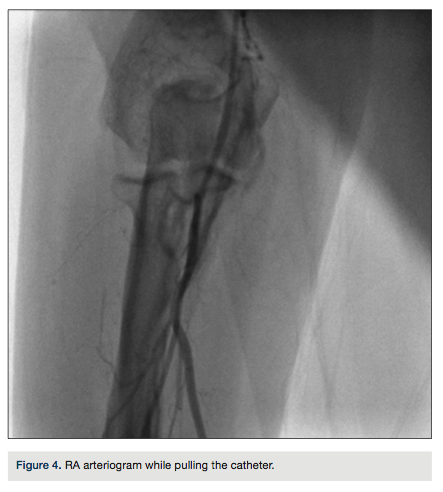

catheter was inserted up to the proximal axillary artery over the wire (Figure 3). The wire was exchanged for a 0.035-inch, 260-cm long wire through the catheter. During left heart catheterization, this wire maintained position in the ascending aorta to exchange the catheters. The patient received 50 units/kg of unfractionated heparin during the procedure. Diagnostic coronary angiography demonstrated normal coronary arteries with mild luminal irregularities. The procedure was completed through the same RA access obtained at the beginning of the procedure. At the end of the left heart catheterization, the catheter was pulled

back over the wire just distal to the perforated segment, and a radial arteriogram was performed while slowly retracting the catheter (Figure 4).